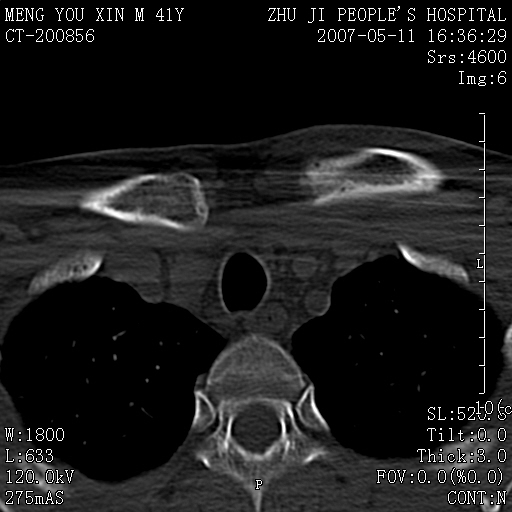

标题: CT8190:左锁骨胸骨端骨病,请会诊.

一周前左肩部酸痛,三天前颈部扭伤,后颈部摄片示颈椎病.现胸锁关节处肿痛明显.无发热.自诉三年前车祸安全气囊弹出.

左侧锁骨近端膨大,骨皮质中断,并见少许骨膜反应,内见破坏,边缘见筛孔征,无硬化.因此考虑骨巨细胞瘤可能.

双侧胸锁关节未见明显异常改变。

1,不支持结核,此例胸壁肿胀不明显,锁骨后方是局限性肿物而非脓肿,考虑为恶性肿瘤2,左侧锁骨近端膨大,骨皮质中断,并见少许骨膜反应,内见破坏,边缘见筛孔征,无硬化.因此考虑骨巨细胞瘤可能.